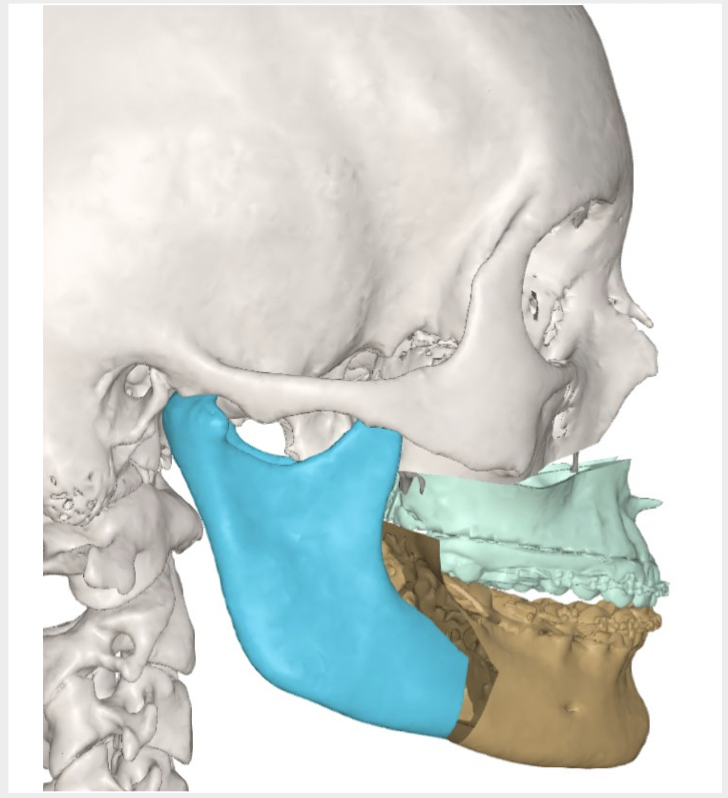

The above video gives an insight into the use of advanced computer simulations and planning software used to create custom titanium plates in a mandibular (lower jaw) reconstruction surgery.